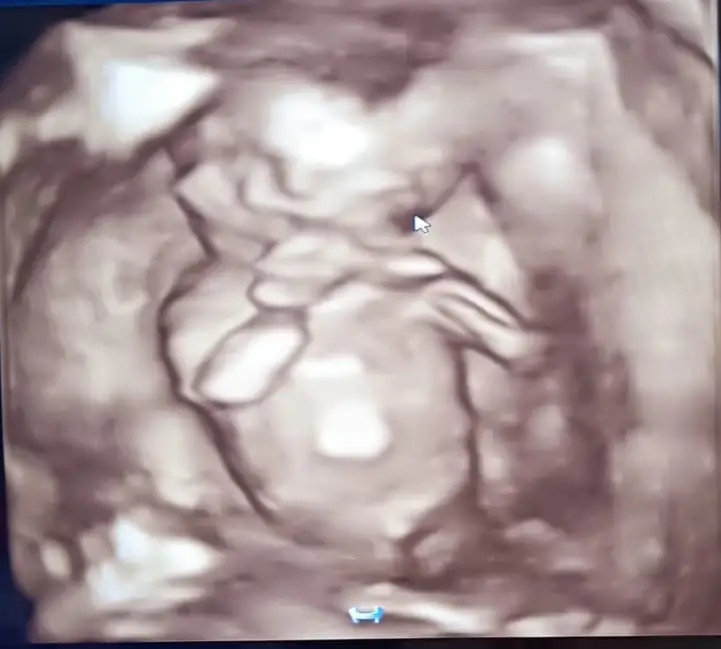

Erkek benceMerhabalar gençler14 haftalık bebişin cinsiyetini tahmin edebilen var mı acaba?